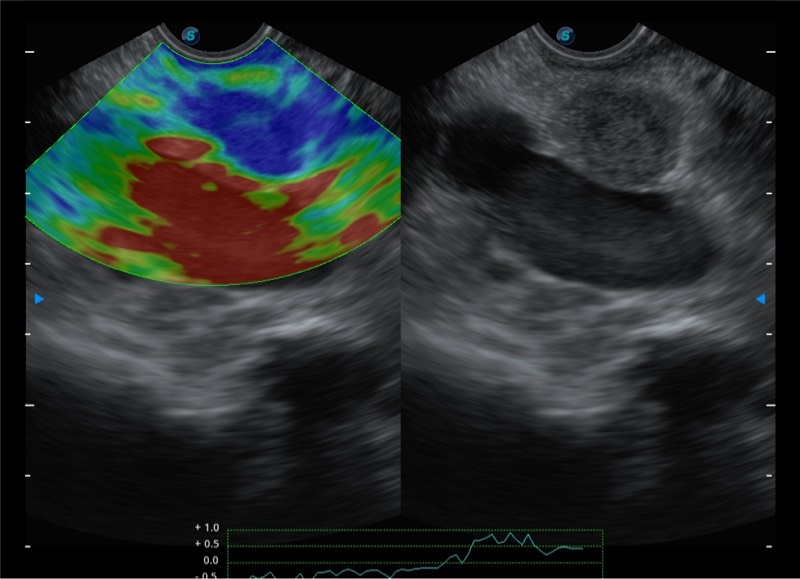

基于二十年的超声技术积累,环球UG官网提供了最新一代的独立超声主机,在提供高质量图像的同时满足多学科使用。具备常见多普勒技术并提供弹性成像、声学造影等高端影像技术。新一代传感器具有更强的抗干扰能力并减少图像伪影。